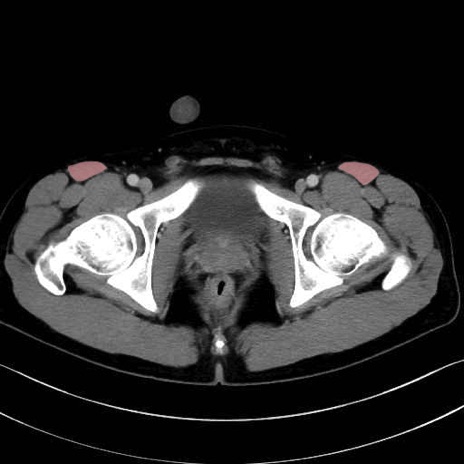

4. 深層外旋六筋(股関節の深部)

梨状筋 (Piriformis)

内閉鎖筋 (Obturator internus)

外閉鎖筋 (Obturator externus)